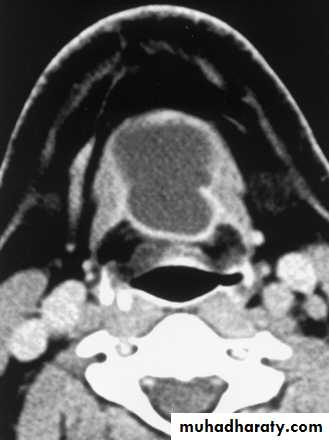

Thyroglossal Duct Cyst

Most common congenital neck mass (70%)50% present before age 20

Midline (90%).

Usually just inferior to hyoid bone (65%)

Painless unless infected.

Elevates on swallowing/protrusion of tongue

Treatment is surgical removal (Sis trunk) after resolution of any infection